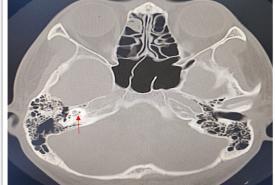

Labyrinthitis Ossificans Post COVID Vaccination

Pansinusitis-associated Superior Subperiosteal Abscess in An Adolescent: A Case Report